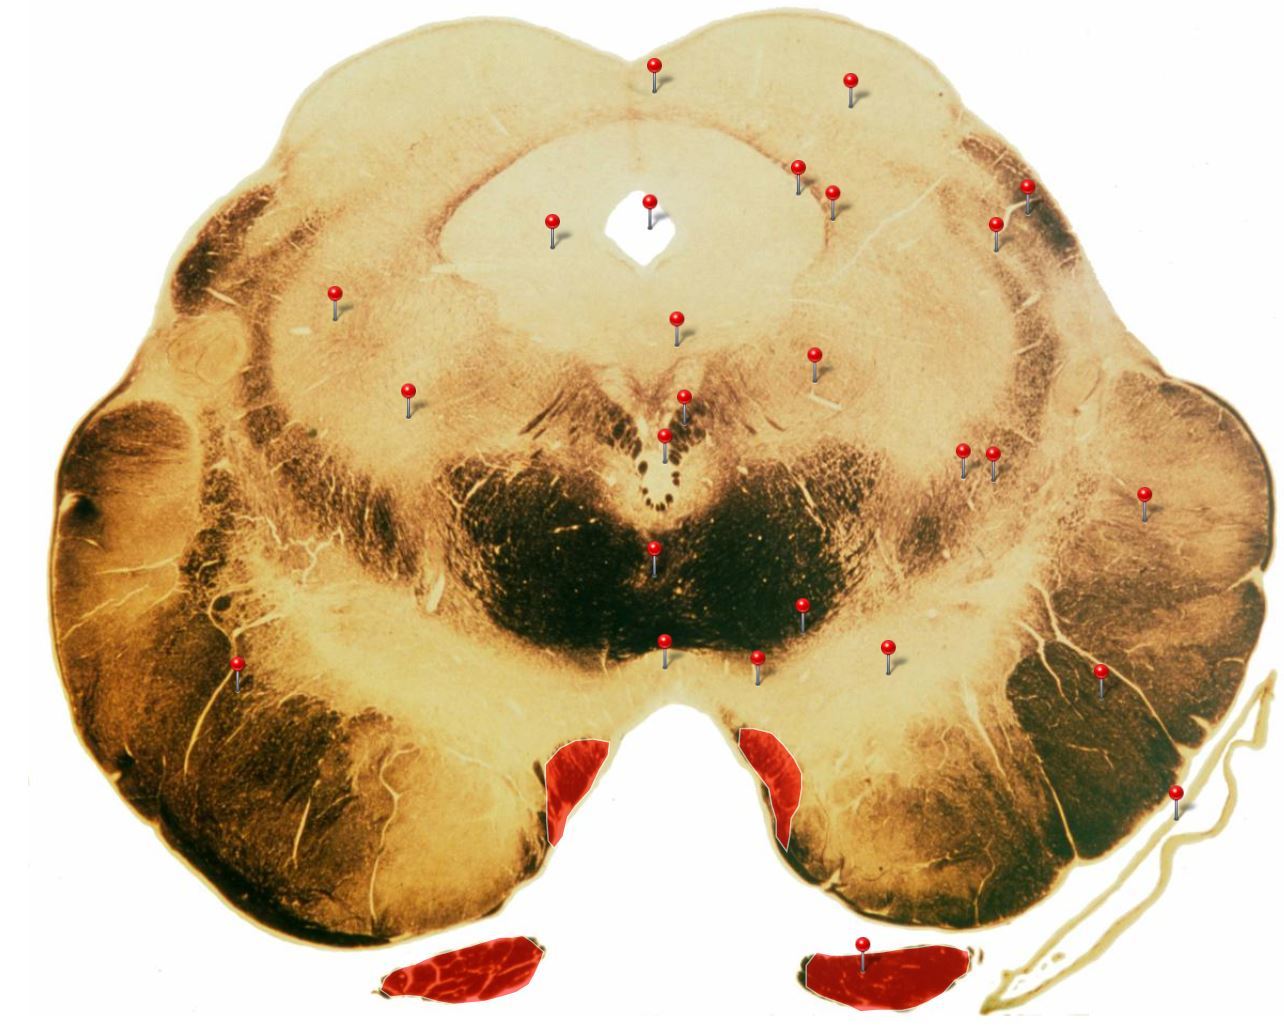

11

Q

Corticospinal Tract

Rostral Medulla

Controls precision and speed of skilled movements involving the distal muscles of the contralateral limbs, particularly those of the hands and fingers

12

Nucleus Ambiguus

Neurons supply the muscles of the pharynx, larynx, upper oesophagus and heart

13

Basilar Artery

Provides blood supply to much of the cerebellum, pons, midbrain and posterior thalamus as well as part of the temporal (inferior surface) and occipital (medial and inferior surfaces) lobes

14

Olives

Elevations formed by the inferior olivary nuclei which integrate information from a variety of sources before relaying it to the cerebellum

15

Rubrospinal Tract

Assists in the control of movements of the hands and fingers

16

Medial Vestibular Nucleus

Process inputs from vestibular receptors of the inner ear and are involved in the regulation of posture and the coordination of head and eye movements

17

Spinal Trigeminal Tract

Transmits somatosensory (crude touch, pain and temperature) inputs from the Trigeminal nerve (CN V) through the midpons and medulla to the spinal trigeminal nucleus.

18

Ventral Cochlear Nuclei

One of the relay nuclei for the auditory fibres of the vestibulocochlear nerve (CN VIII) and functions to modify inputs to the higher auditory structures

19

Medial Longitudinal Fasciculus

Pathway through which eye movements are coordinated with changes in head position

20

Dorsal Cochlear Nuclei

One of the relay nuclei for auditory fibres of the vestibulocochlear nerve (CN VIII) and functions to modify inputs to the higher auditory structures

21

Inferior Olivary Nucleus

Plays an important role in the learning of new motor skills

22

Solitary Nucleus

Processes visceral afferent (GVA and SVA [taste]) inputs from CN VII, IX and X and relays them to the reticular formation and visceral efferent nuclei

23

Spinal Trigeminal Nuclei

Processes sensory inputs, particularly pain and temperature, from the head and neck and relays them to the ventral posteromedial nucleus of the thalamus

24

Inferior Vestibular Nucleus

Plays a role in the maintenance of balance and the coordination of eye and head movements

25

Medial Lemniscus Rostral Medulla Transmits sensations of **discriminative touch, vibration, proprioception** an **stereognosis** from the *gracile* and *cuneate nuclei* to the *ventral posterior nuclei of the thalamus*

26

Ventral Spinocerebellar Tract Rostral Medulla Provides feedback to the cerebellum concerning motor activity (including reflexes) in the lumbosacral levels of the spinal cord

27

Glossopharyngeal Nerve (CN IX) Rostral Medulla Transmits taste and tactile sensation from the posterior part of the tongue, pharynx and ear, and visceral sensation from the chemo- and baroreceptors of the carotid body and sinus (also supplies efferent fibres to the otic ganglion and stylopharyngeus m.)

28

Inferior Cerebellar Peduncle Rostral Medulla Formed by pathways passing in both directions between the medulla and cerebellum

29

Tectospinal Tract Rostral Medulla Function in humans not precisely determined; thought to mediate reflex movements of head in response to visual and perhaps auditory stimuli

30

Olivocerebellar Tract Rostral Medulla Transmits information from inferior olivary nucleus to the *contralateral* cerebellum, where it forms the **climbing fibres**

31

Lateral Vestibular Nucleus Rostral Medulla Contains cell bodies of the (lateral) vestibulospinal tract which regulates the activity of **axial** and **proximal** limb muscles in order to **maintain balance and posture**